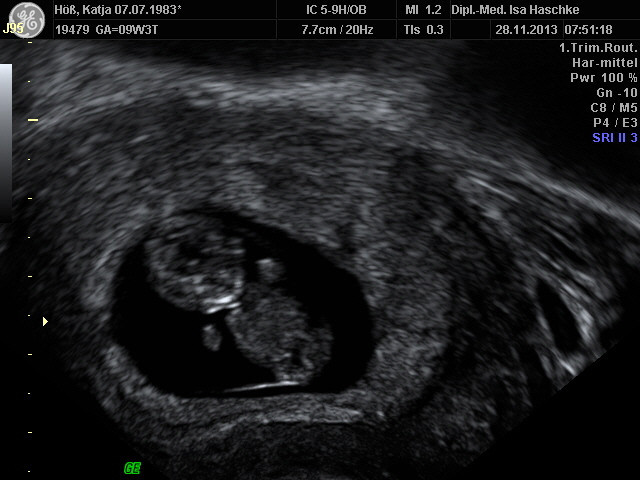

Schwangerschaftswoche 10

Nein ich bin nicht schwanger, hatte nur ein ganzes Ferkel zum Frühstück.

Besonderer Heißhunger:  nur auf Döner und zum trinken Tee

Beschwerden:                 keine Morgenübelkeit; nur leichte Krämpfe

in der Leistengegend

Bauchumfang:                90 cm

Brustumfang:                 96 cm